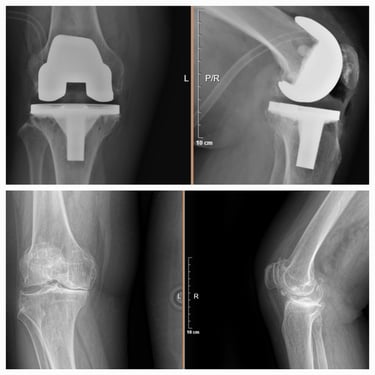

Artroplastia de rodilla (prótesis total/parcial).

Cirugía de revisión de cadera y rodilla.

Manejo de secuelas y complicaciones de prótesis de cadera y rodilla.